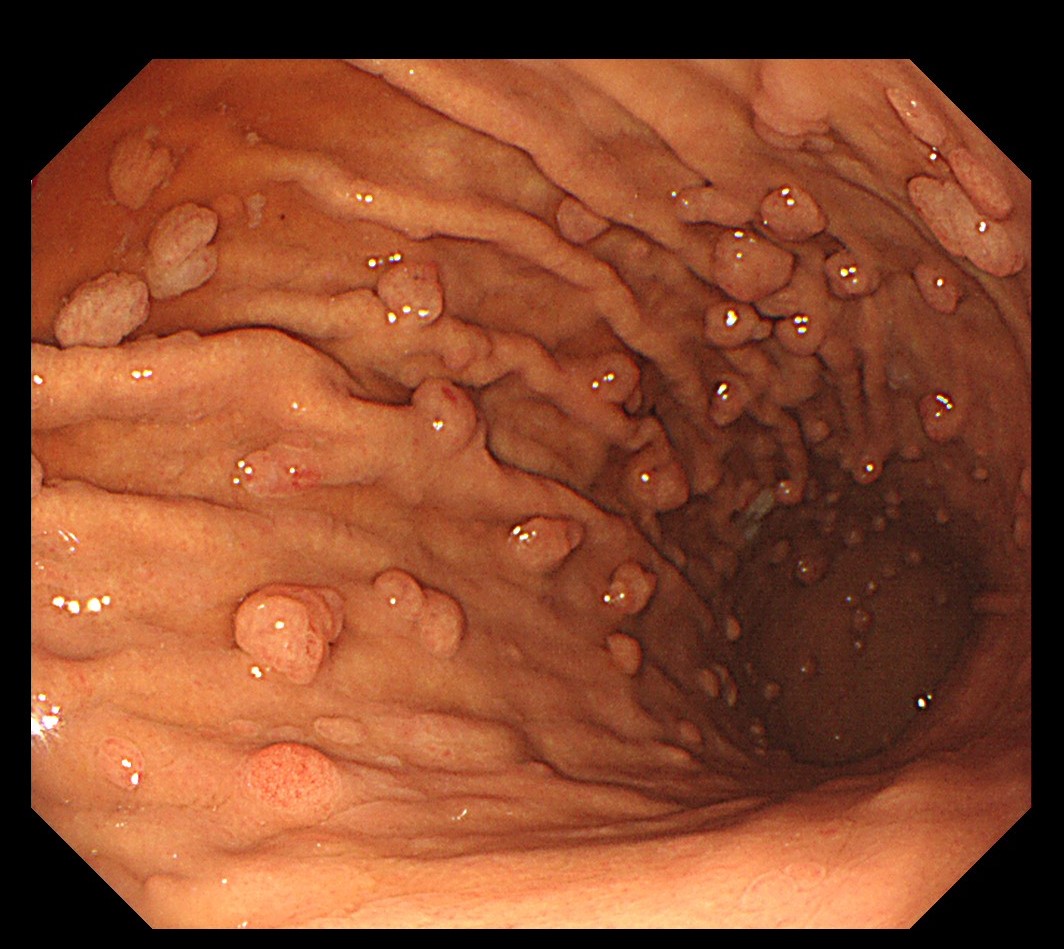

最近、当院を訪れた40代の教師は、普段から食生活や健康に気をつけていましたが、全身健診の胃カメラで驚くべき所見がありました。胃の中に無数のポリープが散らばり、大きさも0.3~1cmとさまざま。あまりの光景に驚かされました。

診断の結果、「多発性胃底腺ポリープ」と判明。胃底腺ポリープはほとんどが良性ですが、1cmを超えるものや表面にただれ・赤み・腫れがある場合はやはり切除が推奨され、長期的な経過観察が必要です。

胃ポリープとは、胃粘膜が増殖してできる隆起性の病変で、単発性または多発性があります。見た目は平坦、乳頭状、または茎を持った腫瘤などさまざまです。

多くの場合、検査を受けるまで自覚症状はありません。サイズは数ミリから数センチまで幅広く、多くは良性ですが、タイプによってはがん化する可能性があるため、特にハイリスク群では注意が必要です。